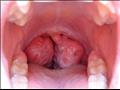

قالت الطبيبة لودميلا لابا، إن اللوزتين تعتبران عضوا هاما في جهاز المناعة في جسم الإنسان، وتعملان كحاجز دفاع واق ضد الالتهابات.

وأضافت: "لذلك يعاني من تم استئصال اللوزتين لديه، بشكل أشد وأقوى عند إصابته بعدوى فيروس كورونا"، وفق ما ذكر موقع "روسيا اليوم".

وذكرت الطبيبة، أن اللوزتين تحميان الإنسان في المقام الأول من الالتهابات البكتيرية، وكما هو معروف -الفيروس التاجي هو عدوى فيروسية.

وقالت: "قد تظهر العدوى البكتيرية على السطح، ولكن من النادر أن تتسرب إلى داخل الجسم، إذا كان جهاز المناعة قويا. ولكن إذا ضعف جهاز المناعة، وبالذات الجهاز اللمفاوي، فستتسلل العدوى إلى هناك. وبما أن الفيروس أقل حجما بكثير فهو يتمكن دائما من دخول الجهاز اللمفاوي، ولذلك يعتبر اعتلال العقد اللمفاوية بمثابة علامة على وجود أي مرض فيروسي. وطبعا عند استئصال اللوزتين، فسيتمكن الفيروس من اختراق الجسم بشكل أعمق، ومن ثم ستتأثر الأعضاء الأخرى، وهو ما سنلاحظه حتما".

وشددت لودميلا لابا، على أن الشخص الذي تم استئصال لوزتيه، سيعاني من المرض بشكل أشد، وستصاب على الفور في جسمه القصبات الهوائية والرئتان وكل ما يتعلق بها. وقالت: "يفقد المرء الحماية فعلا، بعد استئصال اللوزتين".